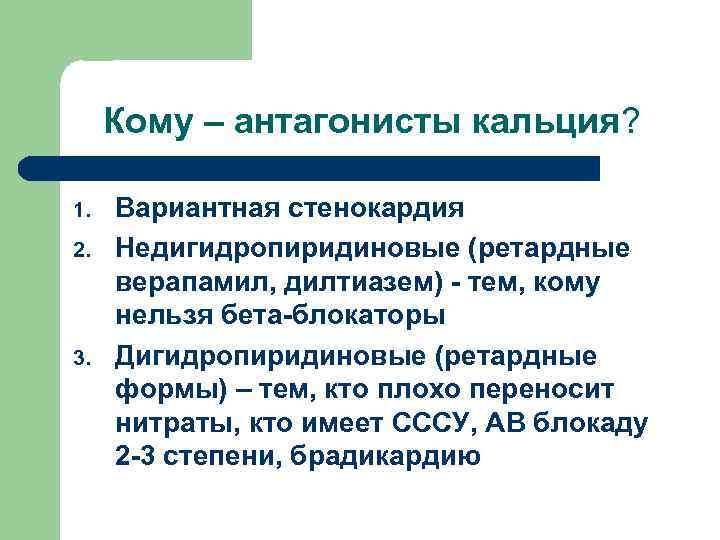

Кому – антагонисты кальция? 1. 2. 3. Вариантная стенокардия Недигидропиридиновые (ретардные верапамил, дилтиазем) - тем, кому нельзя бета-блокаторы Дигидропиридиновые (ретардные формы) – тем, кто плохо переносит нитраты, кто имеет СССУ, АВ блокаду 2 -3 степени, брадикардию